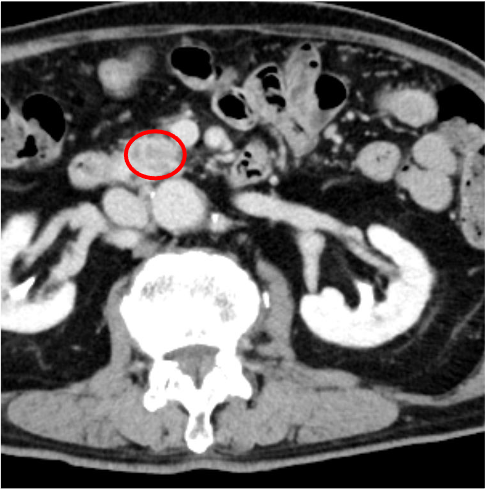

膵癌は、乏血性の境界不明瞭な腫瘤で、造影後期相で漸増性濃染を示すとともに、上流側主膵管の拡張を示すが、本症例はこの典型像に合致していた。主膵管拡張を来す乏血性の腫瘤の鑑別としては、groove pancreatitisなどの良性病変もあるが、膵頭部癌との鑑別は非常に困難とされており1)、疑わしい症例は早期に内視鏡下生検などの精査を依頼するのが望ましい。

本症例では造影CTにて膵頭部に乏血性病変を認めた。Vater乳頭部にも近接していたため、胆膵内視鏡(ERCP)にて検体採取が可能と判断し、病理学的精査を推奨した。消化器内科にて超音波内視鏡下生検(EUS-FNA)を施行、浸潤性膵管癌(invasive ductal adenocarcinoma)の診断が確定した。近傍のSMAへの浸潤はなく、遠隔転移もなかったことから切除可能であり、約7週間後に消化器外科にて膵頭十二指腸切除術を実施、その後順調な経過をたどっている。

CT技術や撮像プロトコル設定について

Photon Counting CTはX線光子を直接電気信号に変換することができる。従来のCTにおいてはX線光子をシンチレータで光信号に変換して、その後フォトダイオードを介して電気信号に変換していたが、Photon Counting CTはこの間接的なプロセスを省略することができる。これによって、空間分解能と画像コントラストが向上し、病変の視認性が良くなる2)。

当院で採用されているNeotom alphaはスライス厚を最小で0.2mmに設定でき、微細な血管まで描出できることから、外科系診療科より術前シミュレーション画像として非常に有益であると好評を得ている。また、Photon Counting CTは信号の変換効率が良いため、従来より低線量かつ高画質の撮像が可能となった。昨今、特に複数回のダイナミック造影を行う肝胆膵領域などにおいて患者の被曝線量の厳密な管理が求められているが、当院でもCare keVなどのプロトコルを用いることで被曝低減につとめている。